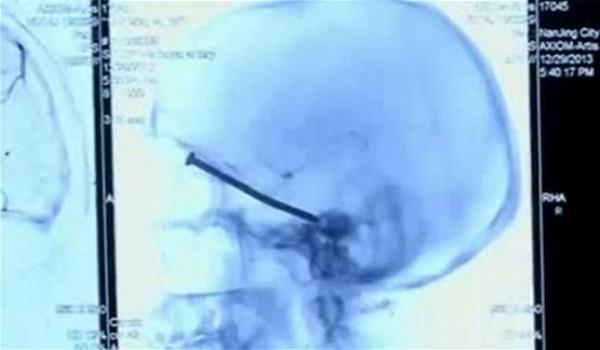

يعيش مع مسمار مغروز في جمجمته دون أن يدري

وعن طريق الخطأ تعرض يانغ يي كوي (55 عاماً) من مقاطعة جيانغسو الصينية لهذه الحادثة أثناء استخدامه آلة قطع خلال تزيين منزله في 29 ديسمبر (كانون الأول)، فكان المسمار الصلب موجوداً داخل الآلة، فانبثق فجأة بسرعة الصاروخ من الآلة ليستقر داخل الدماغ تاركاً فقط حفرة صغيرة في فروة الرأس، وتمكن كوي من معالجتها كأي جرح أو خدش دون أن يعي أو يولي اهتماماً يُذكر بهذا الجرح الصغير، ولم يرد في خاطره على الإطلاق بأن المسمار اخترق جمجمته بل اصطدم برأسه فقط.

وعندما شعر كوي بألم لا يحتمل ومتواصل في رأسه، توجه على الفور إلى المستشفى، ليكتشف بمحض الصدفة وعن طريق الأشعة المقطعية وجود مسمار صلب طوله 3 إنش، فأجرى الأطباء عملية جراحية سريعة لإخراج هذا المسمار من رأسه، بعد أن توغل داخل السائل الدماغي ليستقر بقرب محجر العين اليسرى، دون أن يتسبب بأي ضرر أو أذى يُذكر في الدماغ أو العين، وأكد الأطباء أن حالة يانغ في الوقت الراهن مستقرة ولكنه لا يزال يمكث داخل المستشفى لمتابعة حالته أولاً بأول.